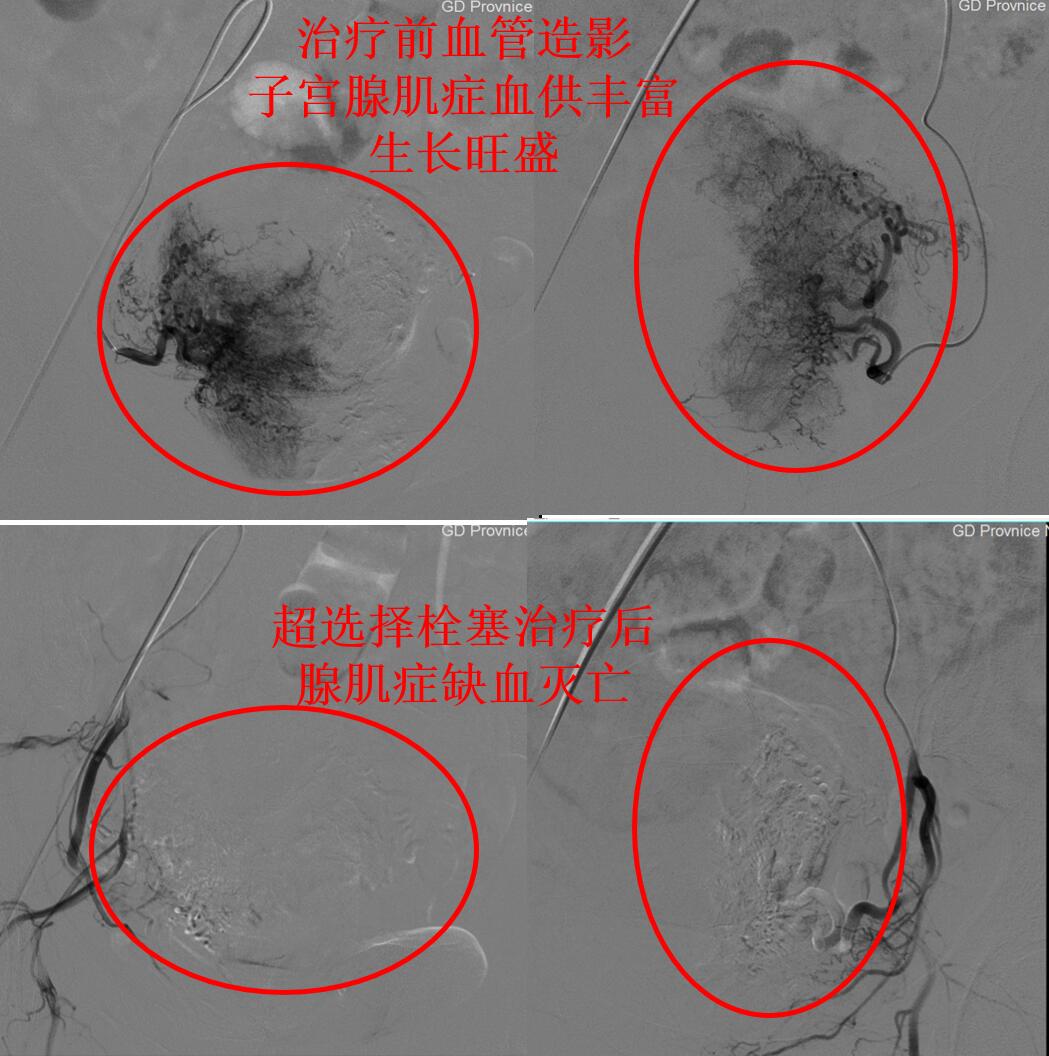

通过CTA评估显示张女士的子宫腺肌症血供丰富,经大腿打针超选择栓塞子宫腺肌症的供血血管杀死腺肌症病灶会取得良好的疗效,则行子宫腺肌病介入超选择栓塞治疗(如下图)。

上图为介入微创超选择栓塞治疗腺肌症的前后对比